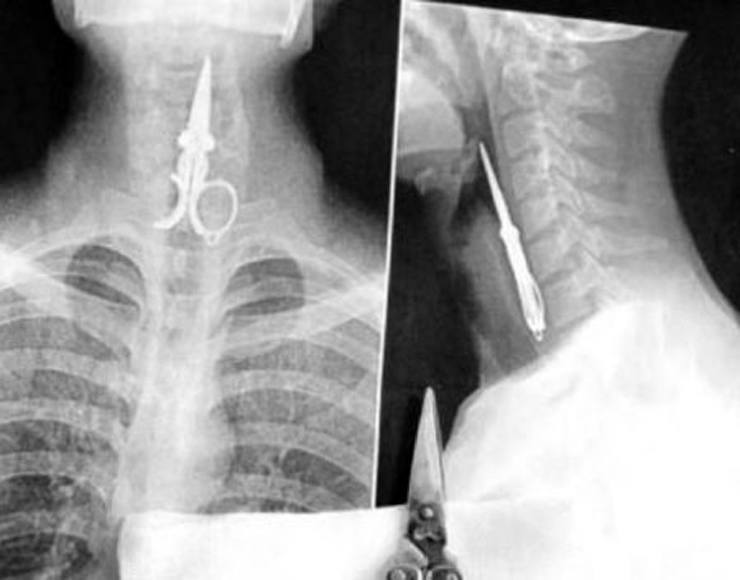

Ножницы

Застрявшие ножницы в горле человека.